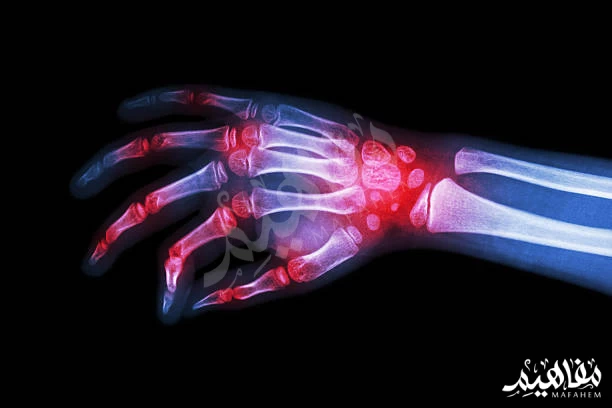

معالجة التهاب المفاصل

- تعدّ آلام التهابات المفاصل من أكثر الألم شيوعا في الوقت الحاضر، ثم أن الأسماك يؤدّي دور كبير في التخلص من هذا الألم بصورة كبيرة.

- وهي إلى ذلك تساعد في تقوية العضلات والأعصاب نظرا لما تمد الجسم به من معادن وفيتامينات ومن أشهر الفيتامينات التي تساعد في بناء وتقوية الأعصاب داخل جسم الإنسان الذي توفره الأسماك بصورة كبيرة هو فيتامين ه.

- ومن الأمراض المناعية التي تساعد الأسماك بصورة كبيرة في علاجها التصلب المتعدد والتهابات المفاصل